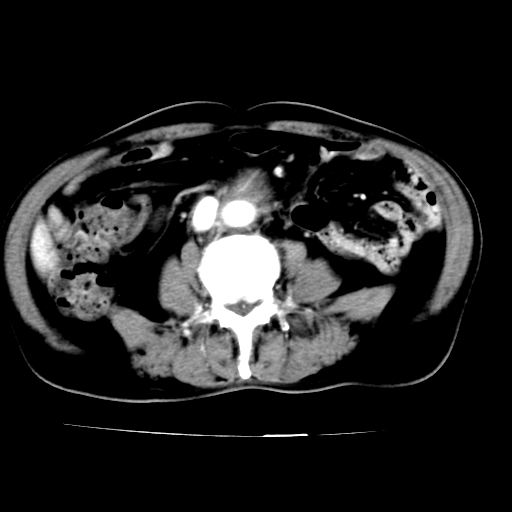

男,75岁,腹痛月余,彩超发现脐周腹主动脉异常回声。临床诊断:腹主动脉瘤。

ct诊断:右骼总动脉囊性动脉瘤并瘤内附壁血栓形成,与下腔静脉之间形成动静脉瘘。

请问各位老师:能排除动脉瘤破裂的可能吗?

各位老师注意到下腔静脉的充盈缺损了吗?注意到动静脉漏了吗?

当时是扫描的标准动脉期,可是下腔静脉与腹主动脉同步强化且幅度一致。所以我想动静脉瘘是存在的。